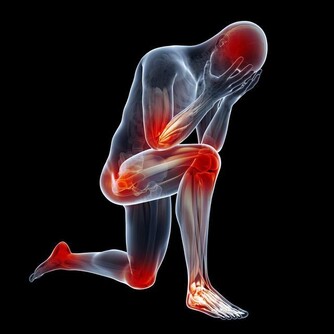

當腦梗出現時,就說明腦部血管出現了堵塞問題,從而表現出異常,影響了對神經的控制,很可能會出現面部神經不受控制的現象,比如面癱、流口水、四肢無力等等。

2、持續性四肢麻木

8、四肢無力